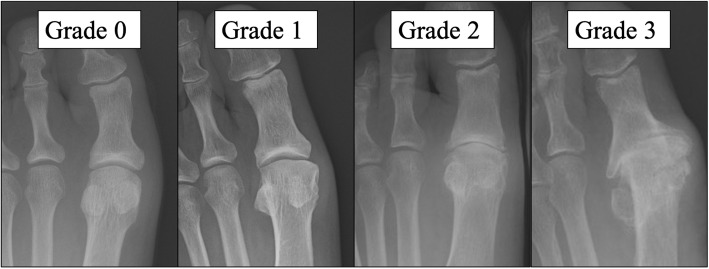

Knee X-rays were taken with the patient standing, knee fully extended. KOA was scored according to the Kellgren-Lawrence grading system [13]. Radiographic KOA was defined as grade 2 or higher. We also took foot X-rays with the participant standing upright with both feet on the cassette, as described by Saltzman et al. [14]. Severity of HR was scored based on the modified version of the Hattrup and Johnson classification [15]. Accordingly, severity of HR was classified as: Grade 0, normal; Grade 1, preservation of joint space, mild osteophyte formation; Grade 2, mild to moderate joint space narrowing, moderate osteophyte formation, subchondral sclerosis and cysts; and Grade 3, severe joint space narrowing, significant osteophyte formation, loose bodies, subchondral sclerosis and cysts (Fig. 2). Radiographic HR was defined as grade 1 or higher, with normal appearance classed as grade 0. Cases with a HV angle of 20° or higher were defined as showing HV.

Severity of hallux rigidus. Grade 0: Normal. Grade 1: Preservation of joint space, mild osteophyte formation. Grade 2: Mild to moderate joint-space narrowing, moderate osteophyte formation, subchondral sclerosis and cysts. Grade 3: Severe joint-space narrowing, significant osteophyte formation, loose bodies, subchondral sclerosis and cysts